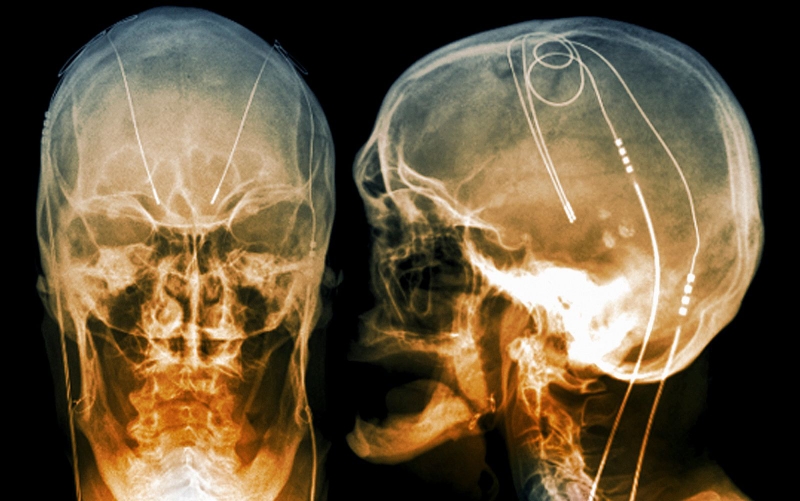

Trong phẫu thuật kích thích não sâu, các bác sĩ sẽ tiến hành cấy điện cực vào một phần cụ thể trong não của người bệnh. Các điện cực này được kết nối với một loại máy phát điện, chúng được cấy vào ngực gần với xương đòn của người bệnh. Máy này có nhiệm vụ phát ra các xung điện tới vị trí cấy điện cực trong não và giúp làm giảm bớt các triệu chứng của bệnh Parkinson.

Bác sĩ có thể điều chỉnh những thiết lập của thiết bị để có thể điều trị phù hợp với tình trạng của từng người bệnh. Tuy nhiên, phẫu thuật có thể gây ra một số biến chứng như là nhiễm trùng, đột quỵ hoặc xuất huyết não. Một số người gặp phải vấn đề với hệ thống kích thích não sâu hoặc là bị biến chứng do kích thích khiến bác sĩ cần điều chỉnh hoặc là thay thế một số bộ phận của thiết bị.

Kích thích não sâu thường được chỉ định đối với những người mắc bệnh Parkinson trong giai đoạn tiến triển có đáp ứng thuốc kém (ví dụ là thuốc levodopa). Hệ thống kích thích não sâu có thể giúp làm giảm các biến chứng vận động của thuốc, giảm hoặc là tạm dừng các rối loạn vận động, giảm run, giảm độ cứng cũng như cải thiện tình trạng chuyển động chậm.

Mặc dù hệ thống kích thích não sâu có thể mang đến lợi ích lâu dài cho các triệu chứng của Parkinson, tuy nhiên chúng không thể ngăn bệnh Parkinson tiến triển.

Phương pháp phẫu thuật kích thích não sâu